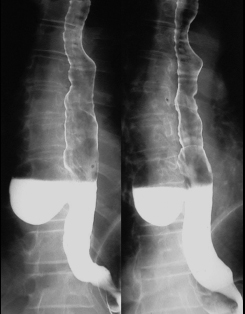

Une portion 1/3 moyen

de oesophage est lisse , dur et aperistaltisme

. Le contrast baryte passa par la est a longue duree

. |

Image radiologique de sclerodermie

de oesophage a partie inferieure audesus de cardia .

Oesophage superieure est dilate |